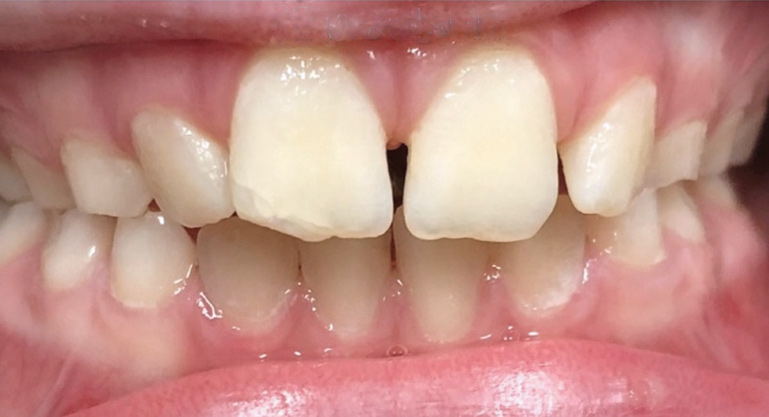

Fig 9. Anteroposterior view of class II (Fig 9) and class III (Fig 10) malocclusion. Arrows indicate positions of the mesial maxillary cusp and embrasure between the mandibular molar cusps. In class II malocclusion the maxillary molar is more anteriorly positioned, while in class III the mandibular molar is more anteriorly positioned.

Figure 9

Fig 10. Anteroposterior view of class II (Fig 9) and class III (Fig 10) malocclusion. Arrows indicate positions of the mesial maxillary cusp and embrasure between the mandibular molar cusps. In class II malocclusion the maxillary molar is more anteriorly positioned, while in class III the mandibular molar is more anteriorly positioned.

Figure 10

Lastly, the anteroposterior dimension is commonly recognized in dental and/or skeletal malocclusions. Skeletal malocclusions are highly prevalent, affecting 27.9% of the US population.26 Interventional treatments are performed predominantly for psychological-social reasons. A class II malocclusion occurs due to an overdeveloped maxilla and/or underdeveloped mandible, relative or absolute. On the contrary, a class III malocclusion presents with a relative or absolute underdeveloped maxilla and/or overdeveloped mandible. Class III malocclusions often have a genetic component in regard to an overdeveloped mandible (eg, "Habsburg jaw" royal family27).

Class II malocclusions (Figure 9) may be treated to reduce risk of dental trauma of protruding maxillary incisors or to break a lip trap habit. Some devices used for this purpose include headgears or functional appliances. Many orthodontists may wait to treat class II malocclusions in the permanent dentition because studies find inconclusive evidence of the effectiveness of phase I treatment.28 Early intervention is a strong consideration for class III malocclusion (Figure 10), with the goal of avoiding surgical treatment for either an adolescent or adult. This approach takes into consideration psychological-social concerns as well with regard to balancing facial disproportions and correcting the appearance of an "underbite" and/or prominent lower jaw.29 However, because there is a genetic component, surgery cannot be ruled out as a comprehensive treatment option. An early intervention would include facemask therapy with RPE to orthopedically protract and widen the upper jaw.